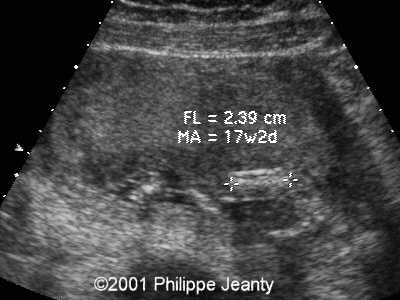

Durante la gravidanza, le donne possono essere sottoposte a screening mediante prelievo di villi coriali (villocentesi) e amniocentesi per rilevare la trisomia 16. Con l'avvento delle tecniche non invasive per la rilevazione dell'aneuploidia, lo screening prenatale con test che utilizzano il sequenziamento di nuova generazione può essere utilizzato prima delle tecniche invasive. Ciò può causare un ritardo della crescita fetale.